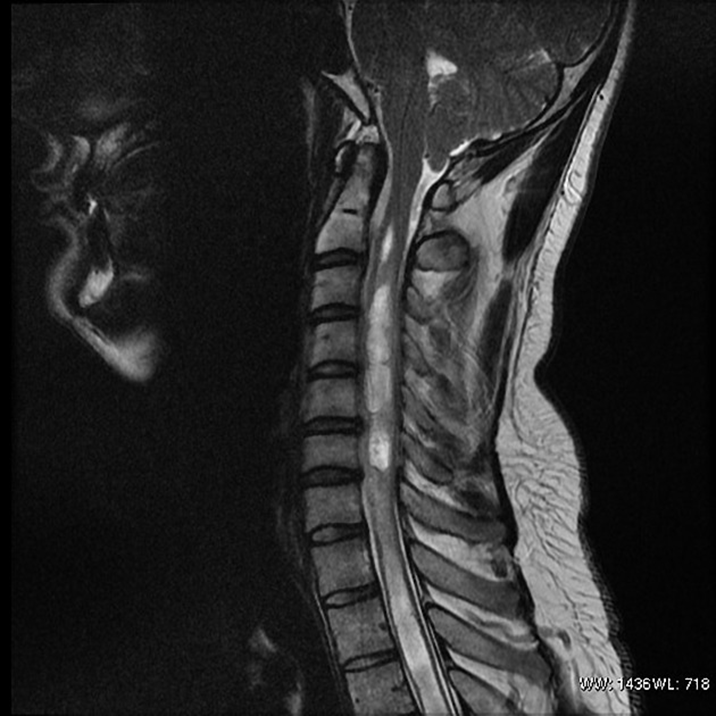

Lumbar spine

Blue DCML

Red ALS spinothalamic tract